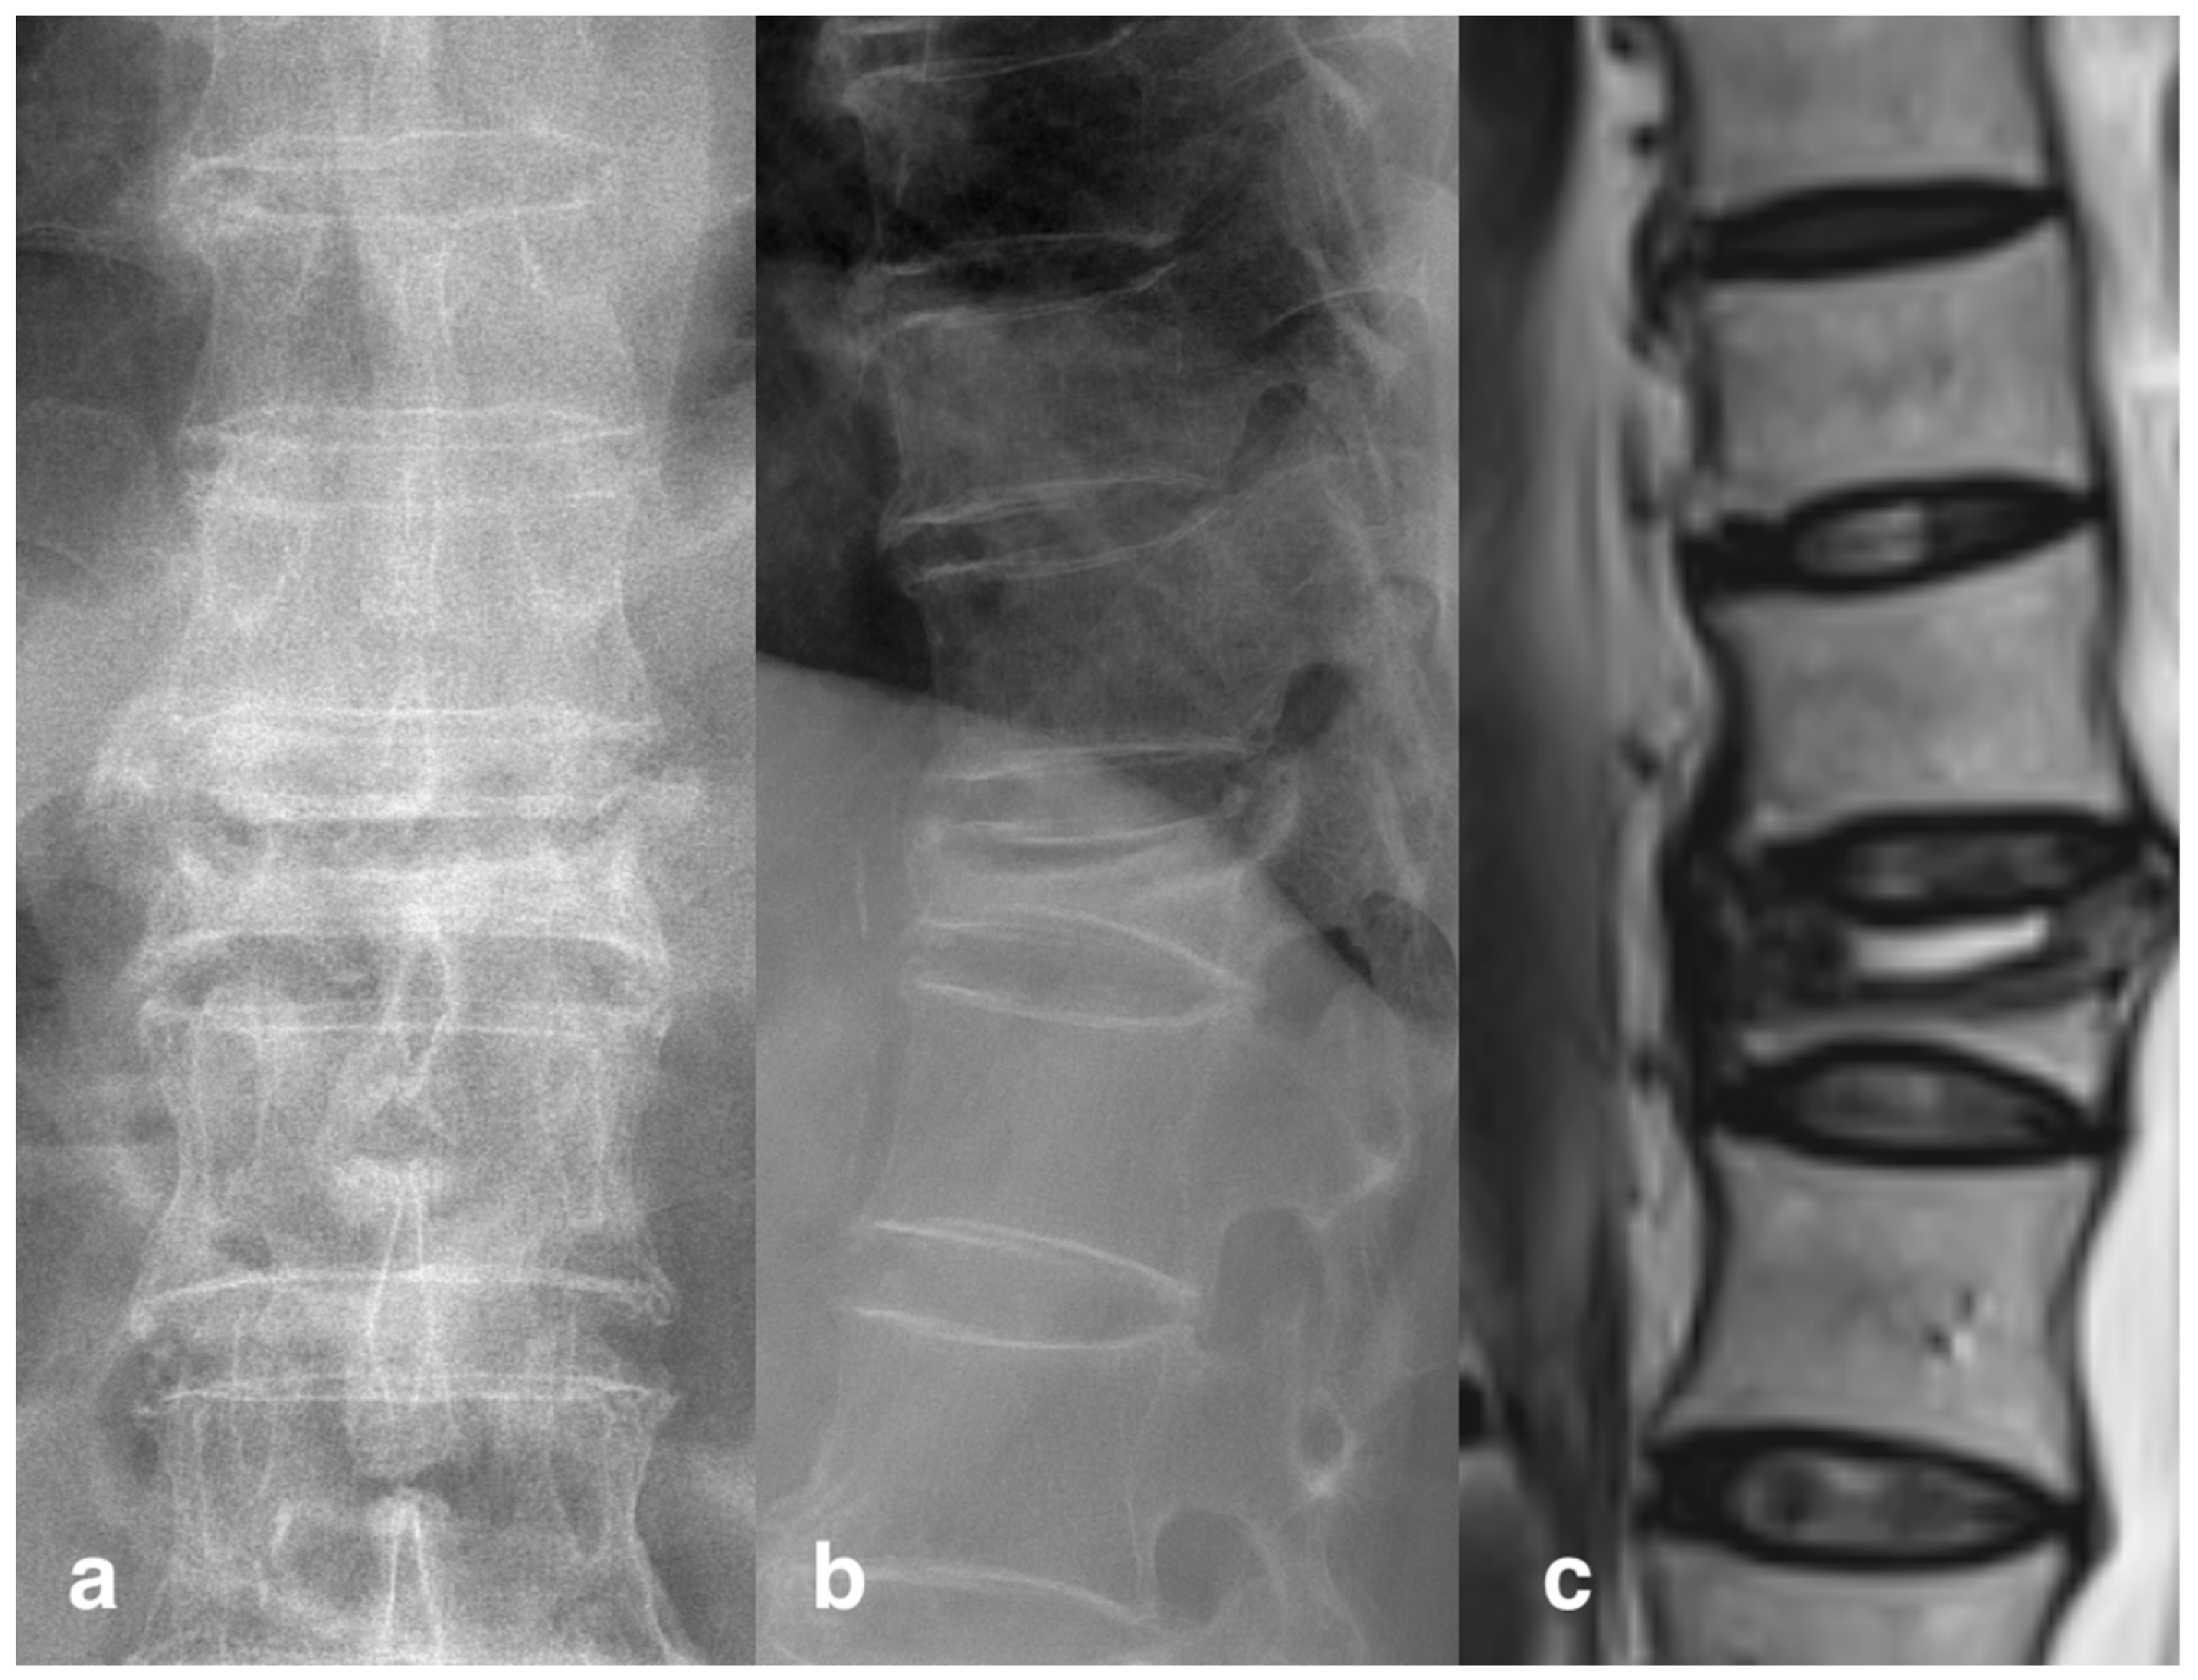

- Theodorou, D.J. The intravertebral vacuum cleft sign. Radiology. 2001, 221, 787–788. [Google Scholar] [CrossRef]

- Libicher, M.; Appelt, A.; Berger, I.; Baier, M.; Meeder, P.J.; Grafe, I.; Dafonseca, K.; Noldge, G.; Kasperk, C. The intravertebral vacuum phenomen as specific sign of osteonecrosis in vertebral compression fractures: Results from a radiological and histological study. Eur. Radiol. 2007, 17, 2248–2252. [Google Scholar] [CrossRef]

| Cleft sign positive (n/%) | 20 (28.6%) | 24 (36.4%) | 0.332 | |